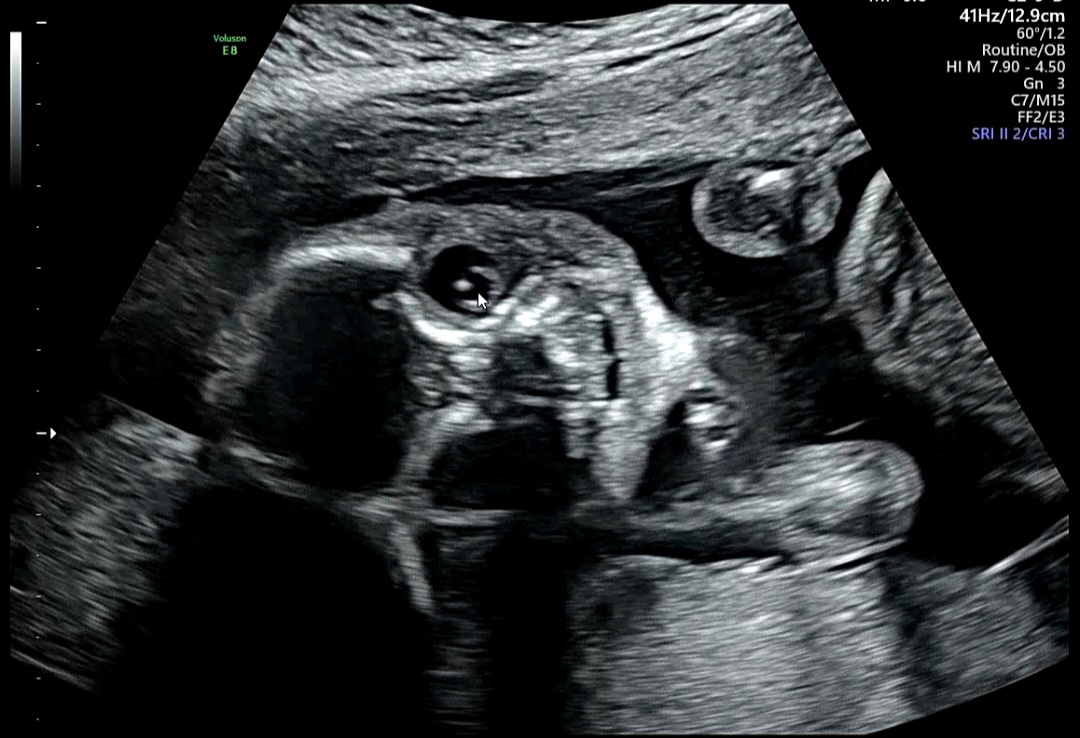

🩺 20주 3일 중기 정밀초음파 후기

드디어 기다리던 중기 정밀초음파!

이 검사는 보통 임신 20~22주에 진행하며,

태아의 장기·사지·뇌·심장 등을 정밀하게 관찰해 기형 여부를 확인한다.

검사는 약 20~30분 소요되며,

태아의 주요 장기 구조를 하나씩 확인하면서 다양한 의학 용어가 등장한다.

까먹기 전에 정리해둔 초음파 용어와 결과를 아래에 남겨둔다.

7. 얼굴 발달 확인

1) NOSE(코)/LIP(입술)

2) LT EAR(왼쪽 귀)/RT EAR(오른쪽 귀)

3) 양쪽 안구

정밀 초음파에서 보는 항목이 많기 때문에 하나하나 자세히 보고 까먹지 않으려고 애썼다.

꿀떡이가 주먹을 쥐고 있는 바람에 손가락 개수 세는 것도 쉽지 않았다.

이 시기에 진행하는 정밀 초음파에서는 신체의 기형을 70%의 정확도로 진단할 수 있다고 한다.

다행히 모든 항목에서 정상소견을 보여 잘 자라준 꿀떡이에게 고마울 따름이다.